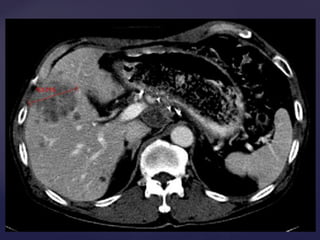

• 30.

 Mejora variable Incluir el hipervascular, si está presente, en la medida más larga de diámetro. Medir el diámetro más largo, independientemente de una necrosis central.